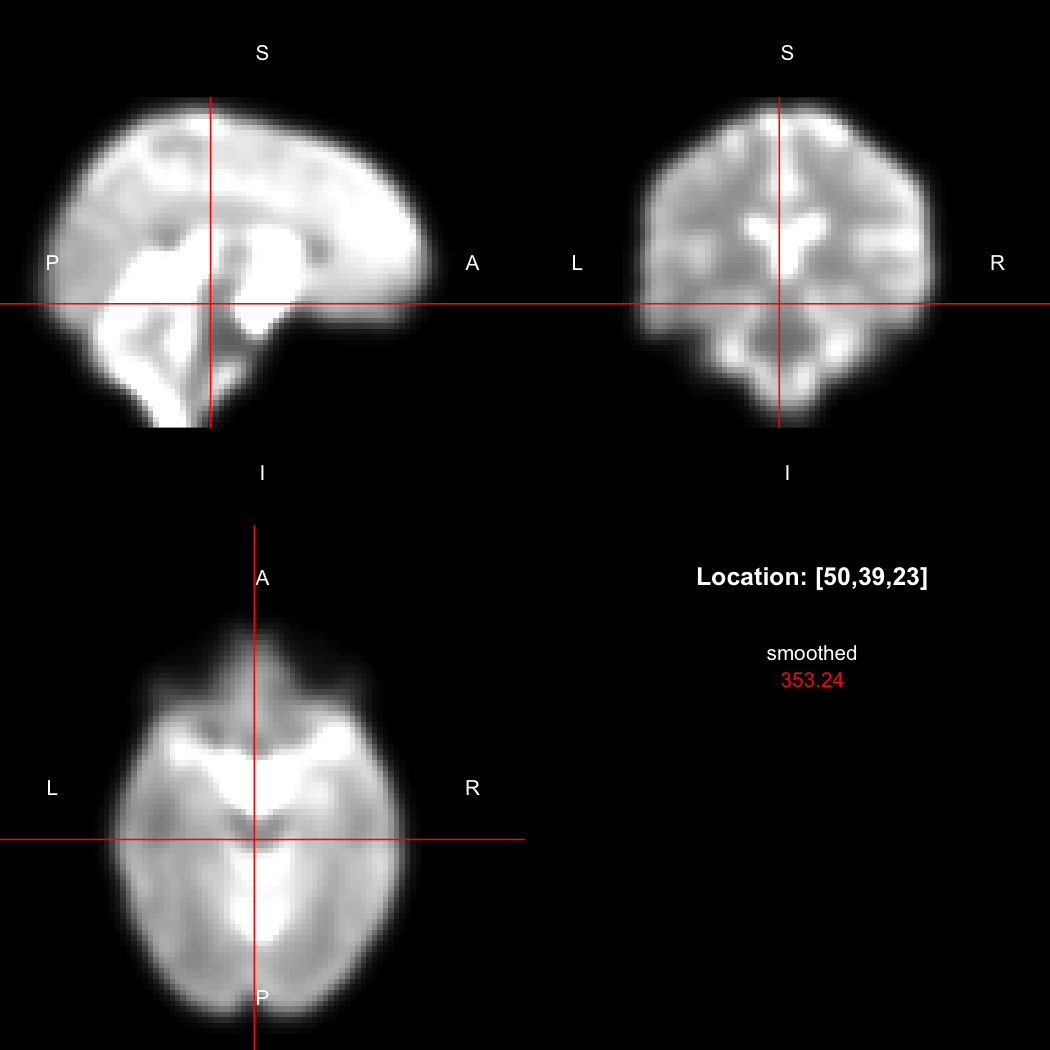

A simple example operation would be to smooth the image with a Gaussian smoothing kernel of standard deviation 4 mm. We can use standard R syntax to perform this operation, return a result, and then show it:

smoothed <- run(smooth_gauss(image, 4))

view(smoothed)

## Setting window to (0, 549.9)

Here, smooth_gauss() requests the smoothing operation,

and run() actually runs the pipeline and returns the

processed image.

However, the pipe syntax provides an alternative, which can be

further simplified because calling view() on a pipeline

will implicitly run it.

image %>% smooth_gauss(4) %>% view()